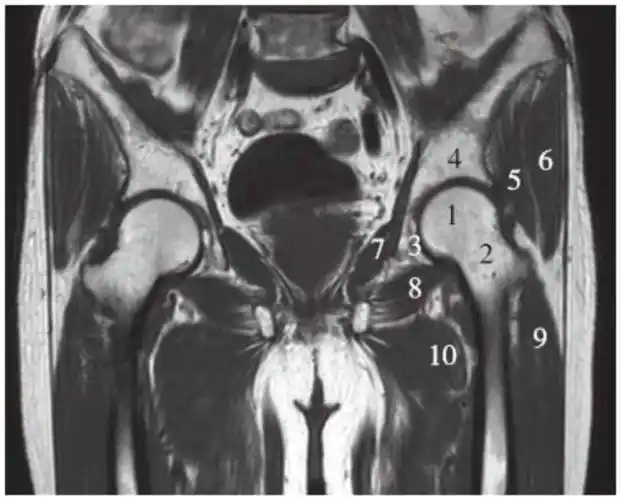

(图) 髋关节mri冠状像(t1加权)-骨科临床解剖学-医学

一文掌握正常髋关节mri解剖示意图